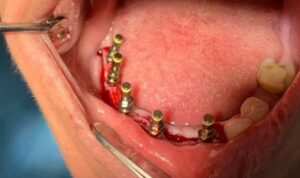

يتم إجراء عمليات الزرع في مراكزنا من قبل فريق من أخصائي زراعة الأسنان ذوي المهارات العالية وأطباء الأسنان التجميليين للحصول على دقة جراحية متميزة وجماليات ممتازة للابتسامة

يترأس مراكزنا فريق مختار بعناية من خبراء زراعة الأسنان. وبعد عملية الزرع يتم تركيب التيجان والجسور ، والتي يتم تصميمها بأقصى قدر من الدقة والجمالية لمنحك الابتسامة المثالية.

يتم تخطيط وتنفيذ إجراء زراعة الأسنان بعناية لضمان أن ترميم الأسنان يبدو طبيعيًا في الشكل واللون والمكان. نعطي الأولوية لراحة مرضانا بالإضافة إلى الجماليات. وهذا يتطلب مزيجًا مثاليًا من العبقرية الفنية والجراحية. لذلك ، يتم تنفيذ جميع حالات الزرع لدينا من قبل فريق من أطباء الأسنان التجميليين وأخصائي زراعة الأسنان.